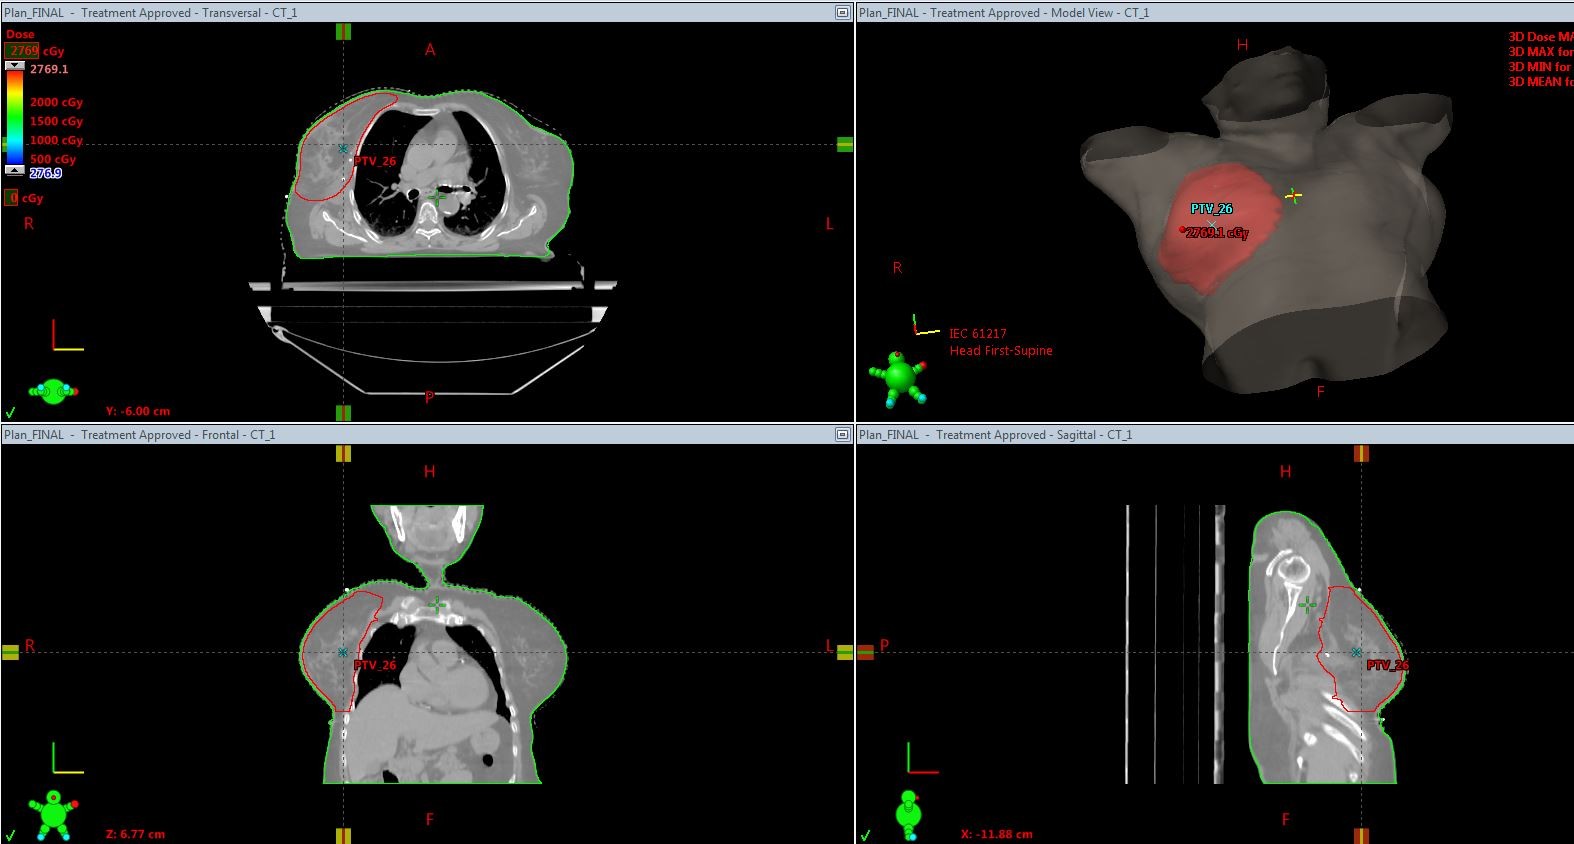

Multiple plans were made for each patient ensuring maximum  dose coverage to the planning target volume,minimizing dose to heart and lung according to the fast forward protocol.The ideal dose coverage for 95% of the target volume is 95% of the dose. The best plan was selected by the radiation oncologist and was executed (Picture 4).

Picture 4-95% dose distribution curve

The following criteria for dose coverage were given as per the fast forward planning pack protocol to get the optimum results.(Table-2).The final decision is taken by the oncologist prioritising normal tissue dose constraints  over the target coverage constraints. Medical physicists aimed at reducing the amount of lung and heart in the treated area by  MLC shielding on the tangential fields and also by shifting the field borders according to the particular case without compromising the position of the area of interest.(8)